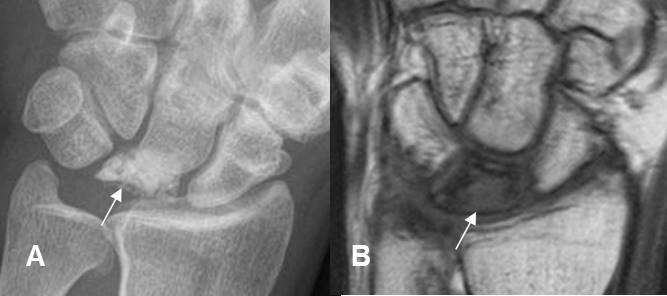

Fig 192. Enfermedad de Kienböck.

A: Rx AP. Hueso semilunar con pérdida de su configuración y aumento de la densidad.

B: RM coronal en T1. Semilunar hipointenso, por la presencia de osteonecrosis.